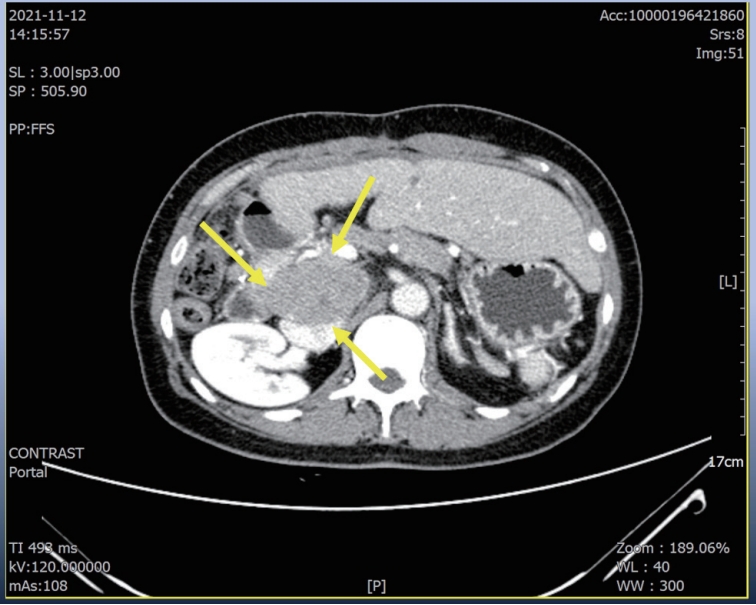

Recently, the survival benefit of immuno-oncologic (IO) agents for advanced hepatocellular carcinoma (HCC) has been proven in several randomized controlled trials. Especially, atezolizumab with bevacizumab (Ate+Beva), as a first-line therapy for advanced HCC, has shown outstanding efficacy in the IMBrave150 study. Fortunately in south Korea, the cost of Ate+Beva therapy can be covered by national medical insurance, therefore HCC patients can receive Ate+Beva therapy without trouble. However, almost all HCC patients have no choice but to stop the treatment after two years completion of Ate+Beva therapy because our national medical insurance only cover IO therapy for two years. Therefore clinicians have been restarting the systemic treatment after confirming the disease progression of HCC patients on resting period of systemic therapy. Here, we report a case that showed a partial response of lymph node metastasis by 3rd line regorafenib therapy for progression of LN metastasis after achieving nearly complete response by two-year completion of 1st line Ate+Beva therapy in advanced HCC patient.